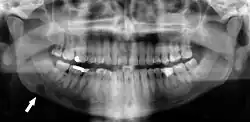

Panoramic radiographs have the capability to demonstrate a portion of the neck and display atheromas (calcifications in the carotid artery) which are an indication of both local and generalized (systemic) atherosclerosis. Atherosclerosis of the coronary arteries leading to myocardial infarction (heart attack), and atherosclerosis of the carotid artery leading to stroke are the number one and number three most common causes of death in the United States.[6]

There is interest to look at panoramic radiographs as a screening tool, however further data is needed with regards if it is able to make a meaningful difference in outcomes.[7]

Epidemiology: general public and high risk groups

Additional research projects have further determined the prevalence rate of these atheromas in the general population (3–5%)[8][9] and among high-risk groups (over 25% in: recent stroke victims,[10] individuals with obstructive sleep apnea syndrome,[11][12][13] postmenopausal women,[14] type 2 diabetics,[15][13][16] individuals with dilated cardiomyopathy,[17][13] and among individuals who have received radiotherapy directed at the neck,[18][19]). These findings have been corroborated by other several other researchers.[20][21][22][23][13]